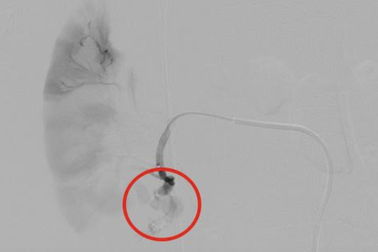

Cứu sống nạn nhân bị dập lách, vỡ thận, máu phun thành vòiSau tai nạn giao thông, nạn nhân được chuyển đến cấp cứu trong tình trạng hôn mê, sốc mất máu nặng. Khi thực hiện cuộc mổ khẩn cấp sau hội chẩn tại giường bệnh, bác sĩ phát hiện lách bệnh nhân bị dập nát, thận bị vỡ, máu đang tuôn thành vòi.